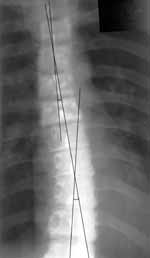

В клинической практике существует несколько методик определения выраженности сколиоза по степеням. Мы предлагаем методику используемую в нашем учреждении. Выполняется прямая рентгенограмма грудного отдела позвоночника в положении больного стоя. Визуально находим центры остистых отростков грудных позвонков и соединяем их между собой (Рис. 2). В норме образуется прямая линия. При сколиозе, соединяющая остистые отростки линия образует дугу (или дуги). На уровне вершины дуги бокового искривления прямые линии, проведенные через остистые отростки выше и ниже лежащих позвонков образуют угол, являющийся углом сколиоза. Углы сколиоза имеют большое значение в решении экспертных вопросов при призыве в армию. На практике при решении комиссионных вопросов применяется следующая градация сколиоза:

Рис. 2. Методика определения выраженности сколиоза по прямой рентгенограмме. Объяснения в тексте.